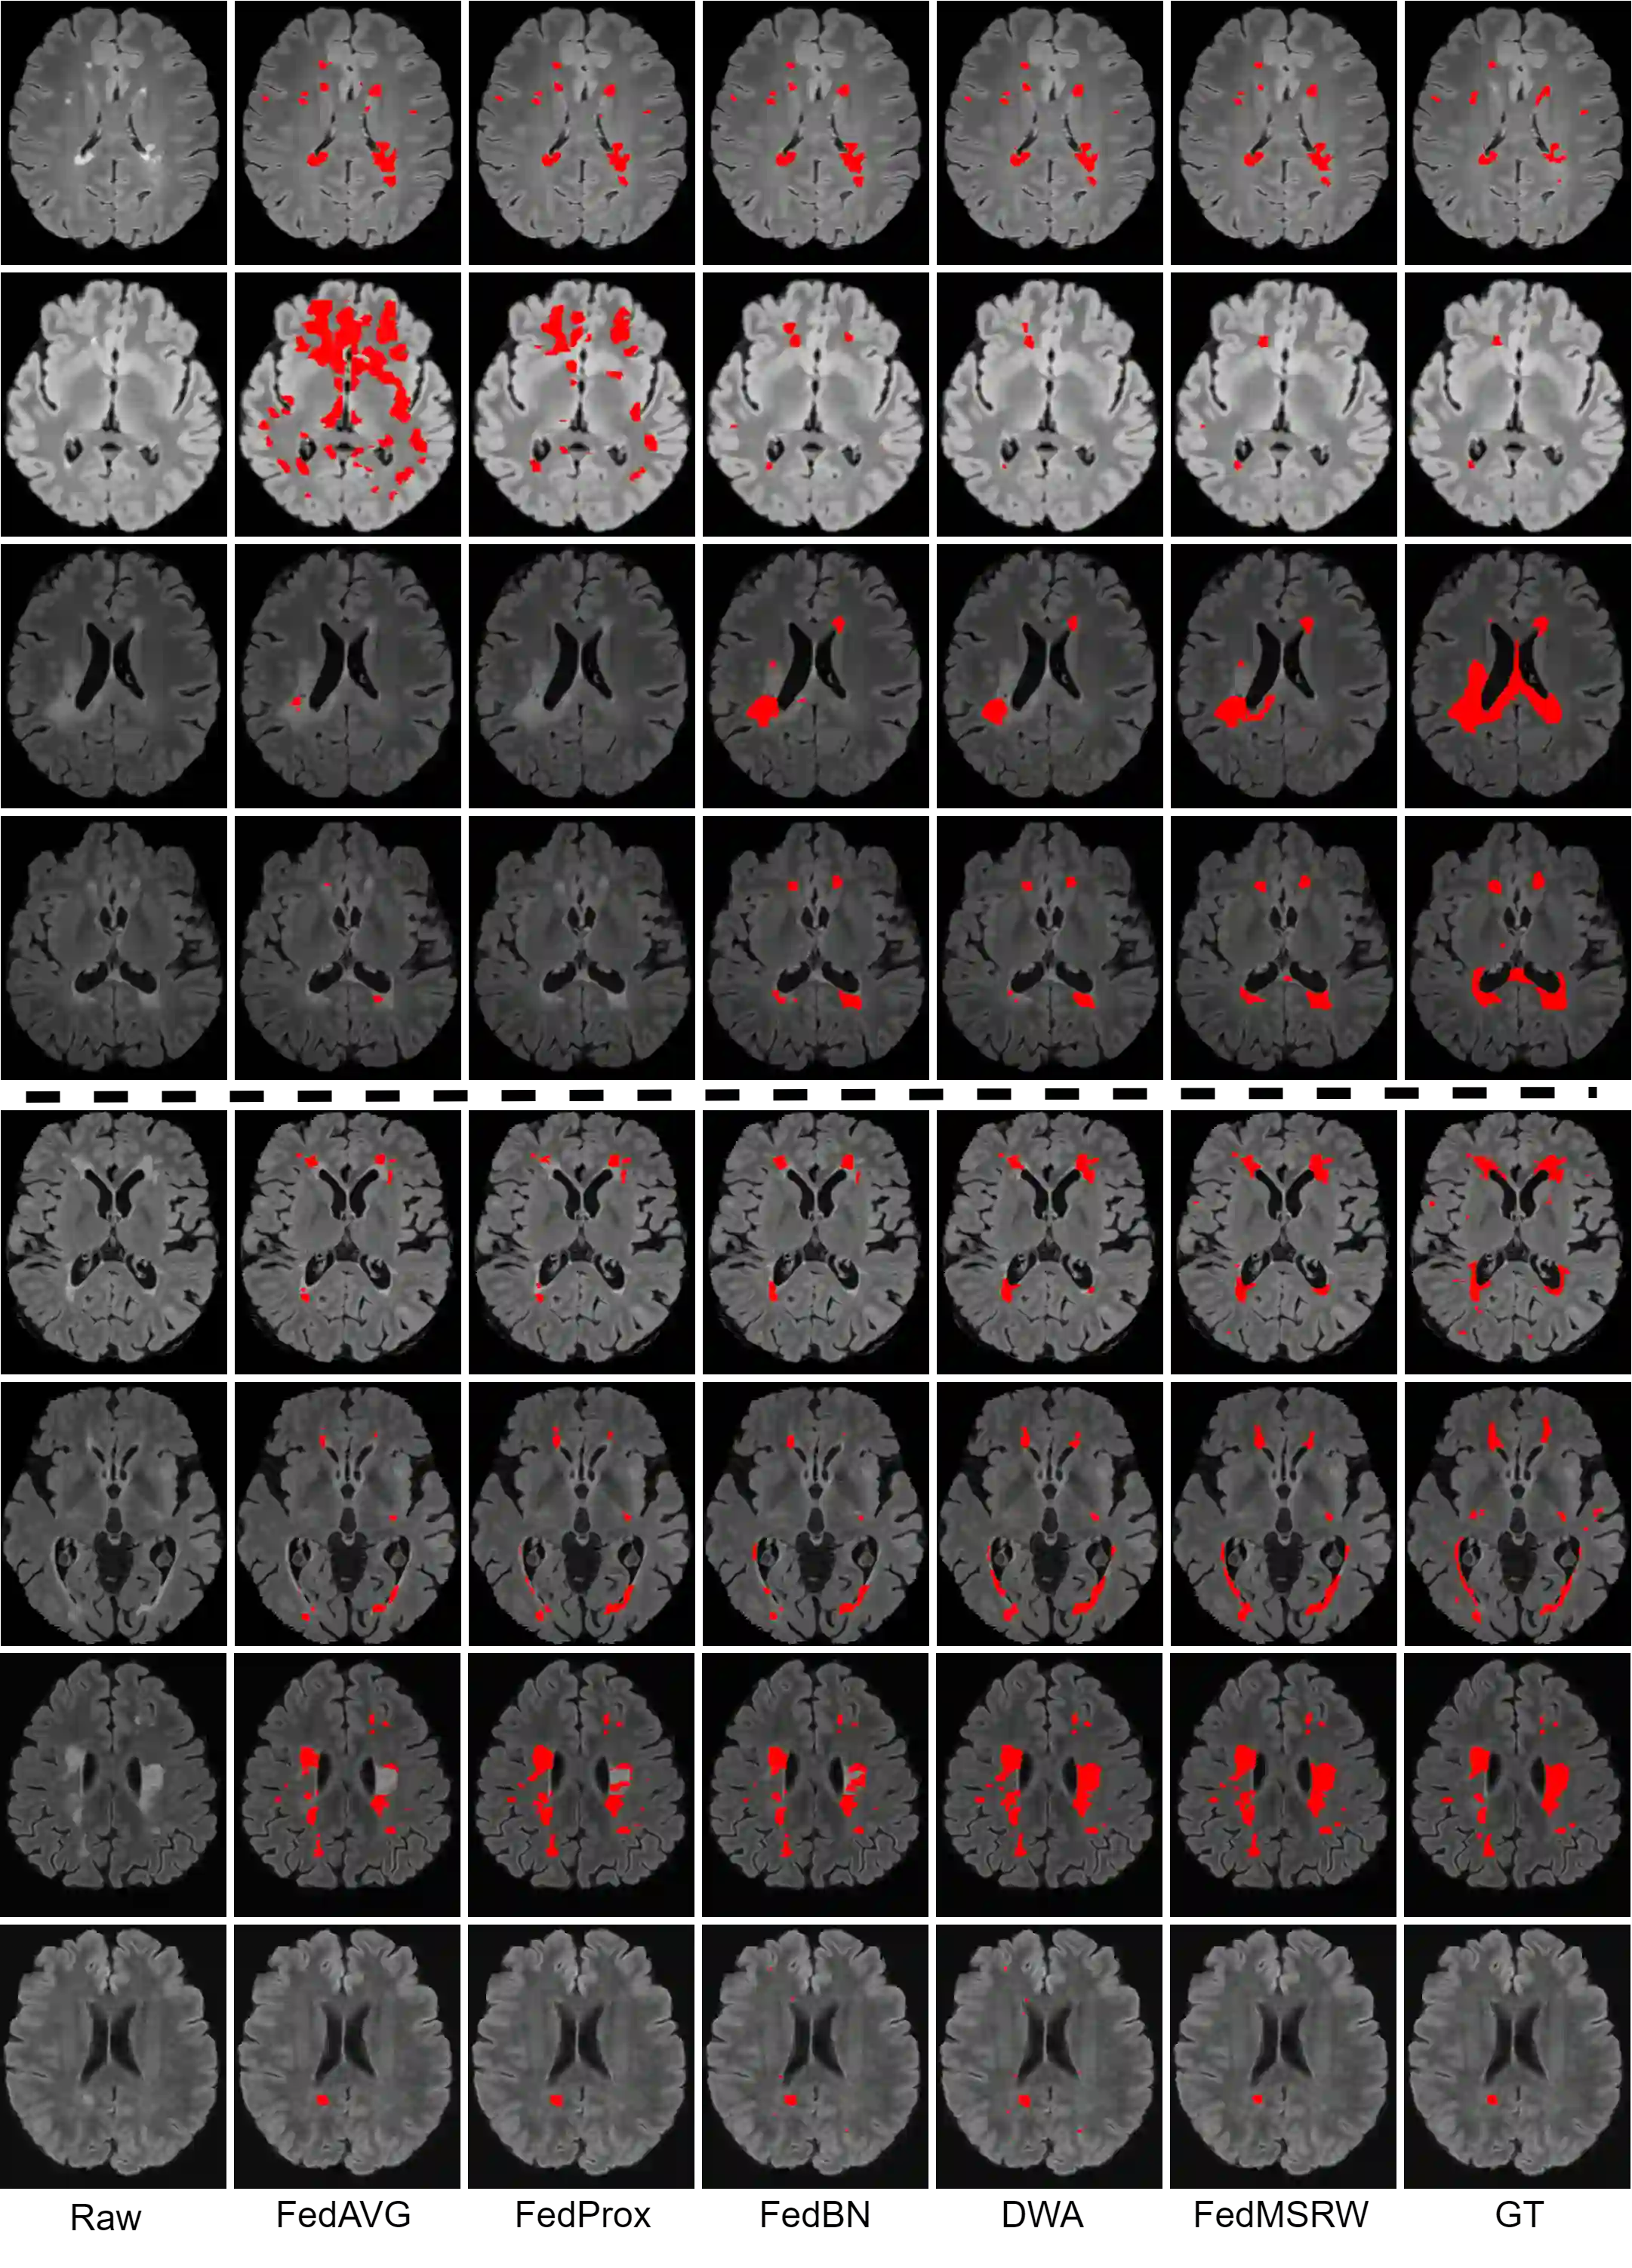

Federated learning (FL) has been widely employed for medical image analysis to facilitate multi-client collaborative learning without sharing raw data. Despite great success, FL's performance is limited for multiple sclerosis (MS) lesion segmentation tasks, due to variance in lesion characteristics imparted by different scanners and acquisition parameters. In this work, we propose the first FL MS lesion segmentation framework via two effective re-weighting mechanisms. Specifically, a learnable weight is assigned to each local node during the aggregation process, based on its segmentation performance. In addition, the segmentation loss function in each client is also re-weighted according to the lesion volume for the data during training. Comparison experiments on two FL MS segmentation scenarios using public and clinical datasets have demonstrated the effectiveness of the proposed method by outperforming other FL methods significantly. Furthermore, the segmentation performance of FL incorporating our proposed aggregation mechanism can exceed centralised training with all the raw data. The extensive evaluation also indicated the superiority of our method when estimating brain volume differences estimation after lesion inpainting.